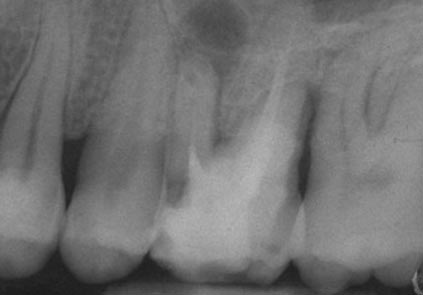

The greater the amount of uncleaned and unfilled canal space that remains after a root canal procedure, the greater failure rate. The challenge for clinicians is to decide to what point endodontic obturation should be directed in the given procedure. Cleaning, shaping and obturating less than the entire root canal space has the potential to or certainly could leave uncleaned and unfilled space, especially if the root is obturated to levels determined by arbitrary anatomic averages and not the true apical foramen.

Root canal overfills occur when a dentist is obturating (filling) a root canal. If the gutta percha(canal filling material) extrudes out the end of the root it is called an overfill. Sometimes, the gutta percha may have slipped through because it was not of sufficient diameter to bind at the apex. If a guttapercha that is too small is used, it can slip thru the tiny apical foramen (a hole at the tip of the root) and the resulting over fill may or may not form good seal . If the gutta percha does not adequately obturate (seal) the apex, then bacteria can repopulate any left over space. This bacterial colonization is most likely the actual cause of most endodontic failures associated with overfills.

WaveOne Reciprocation set a new standard in root canal shaping – allowing most cases to be shaped safely and efficiently with a single file. The metallurgy is now visibly enhanced with a gold thermal treatment – combined with an optimized cross section, tip diameter and taper, it delivers even greater flexibility, resistance to cyclic fatigue and cutting efficiency